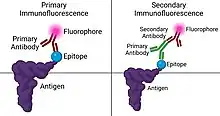

Immunofluorescence

Immunofluorescence is performed by the production of anti-antibodies with a fluorescent molecule attached, making it a chemiluminescent molecule, which provides a glow when subject to ultraviolet light.[13] Antibodies are added to a bacterial solution, providing an antigen for the binding of fluorescent anti-antibody adherence.